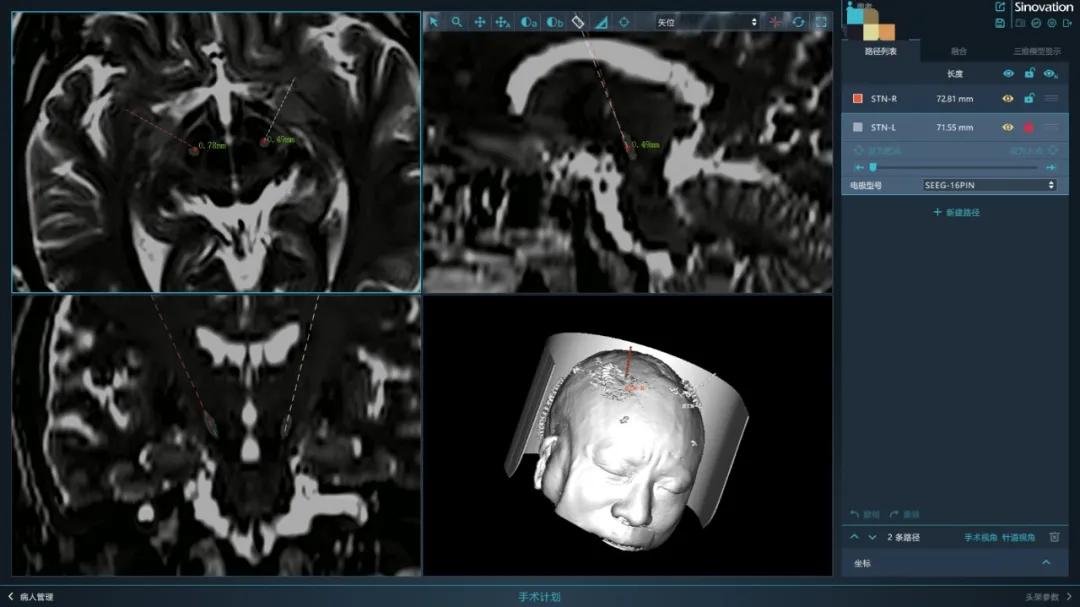

2021年9月7日,江西省人民医院神经外科张建中博士团队借助神经外科手术机器人精确度达0.1mm的“智手”,通过个性化手术设计及精准快速操作,成功为一名帕金森患者进行了微创电极植入手术。据了解,这是我省首例神经外科机器人辅助下脑深部脑电刺激(DBS)手术。

DBS手术最关键的是电极植入的准确性,以往临床采用的是Leksell头架手工调节坐标,有一定的系统误差,并且费时费力。省医神经外科引进的精准手术机器人可以帮助医生更有效的规避颅内血管,将电极沿着事先规划好的手术路径植入颅内,借助机器人更高的精度,能够大幅降低血管和脑组织的损伤率。